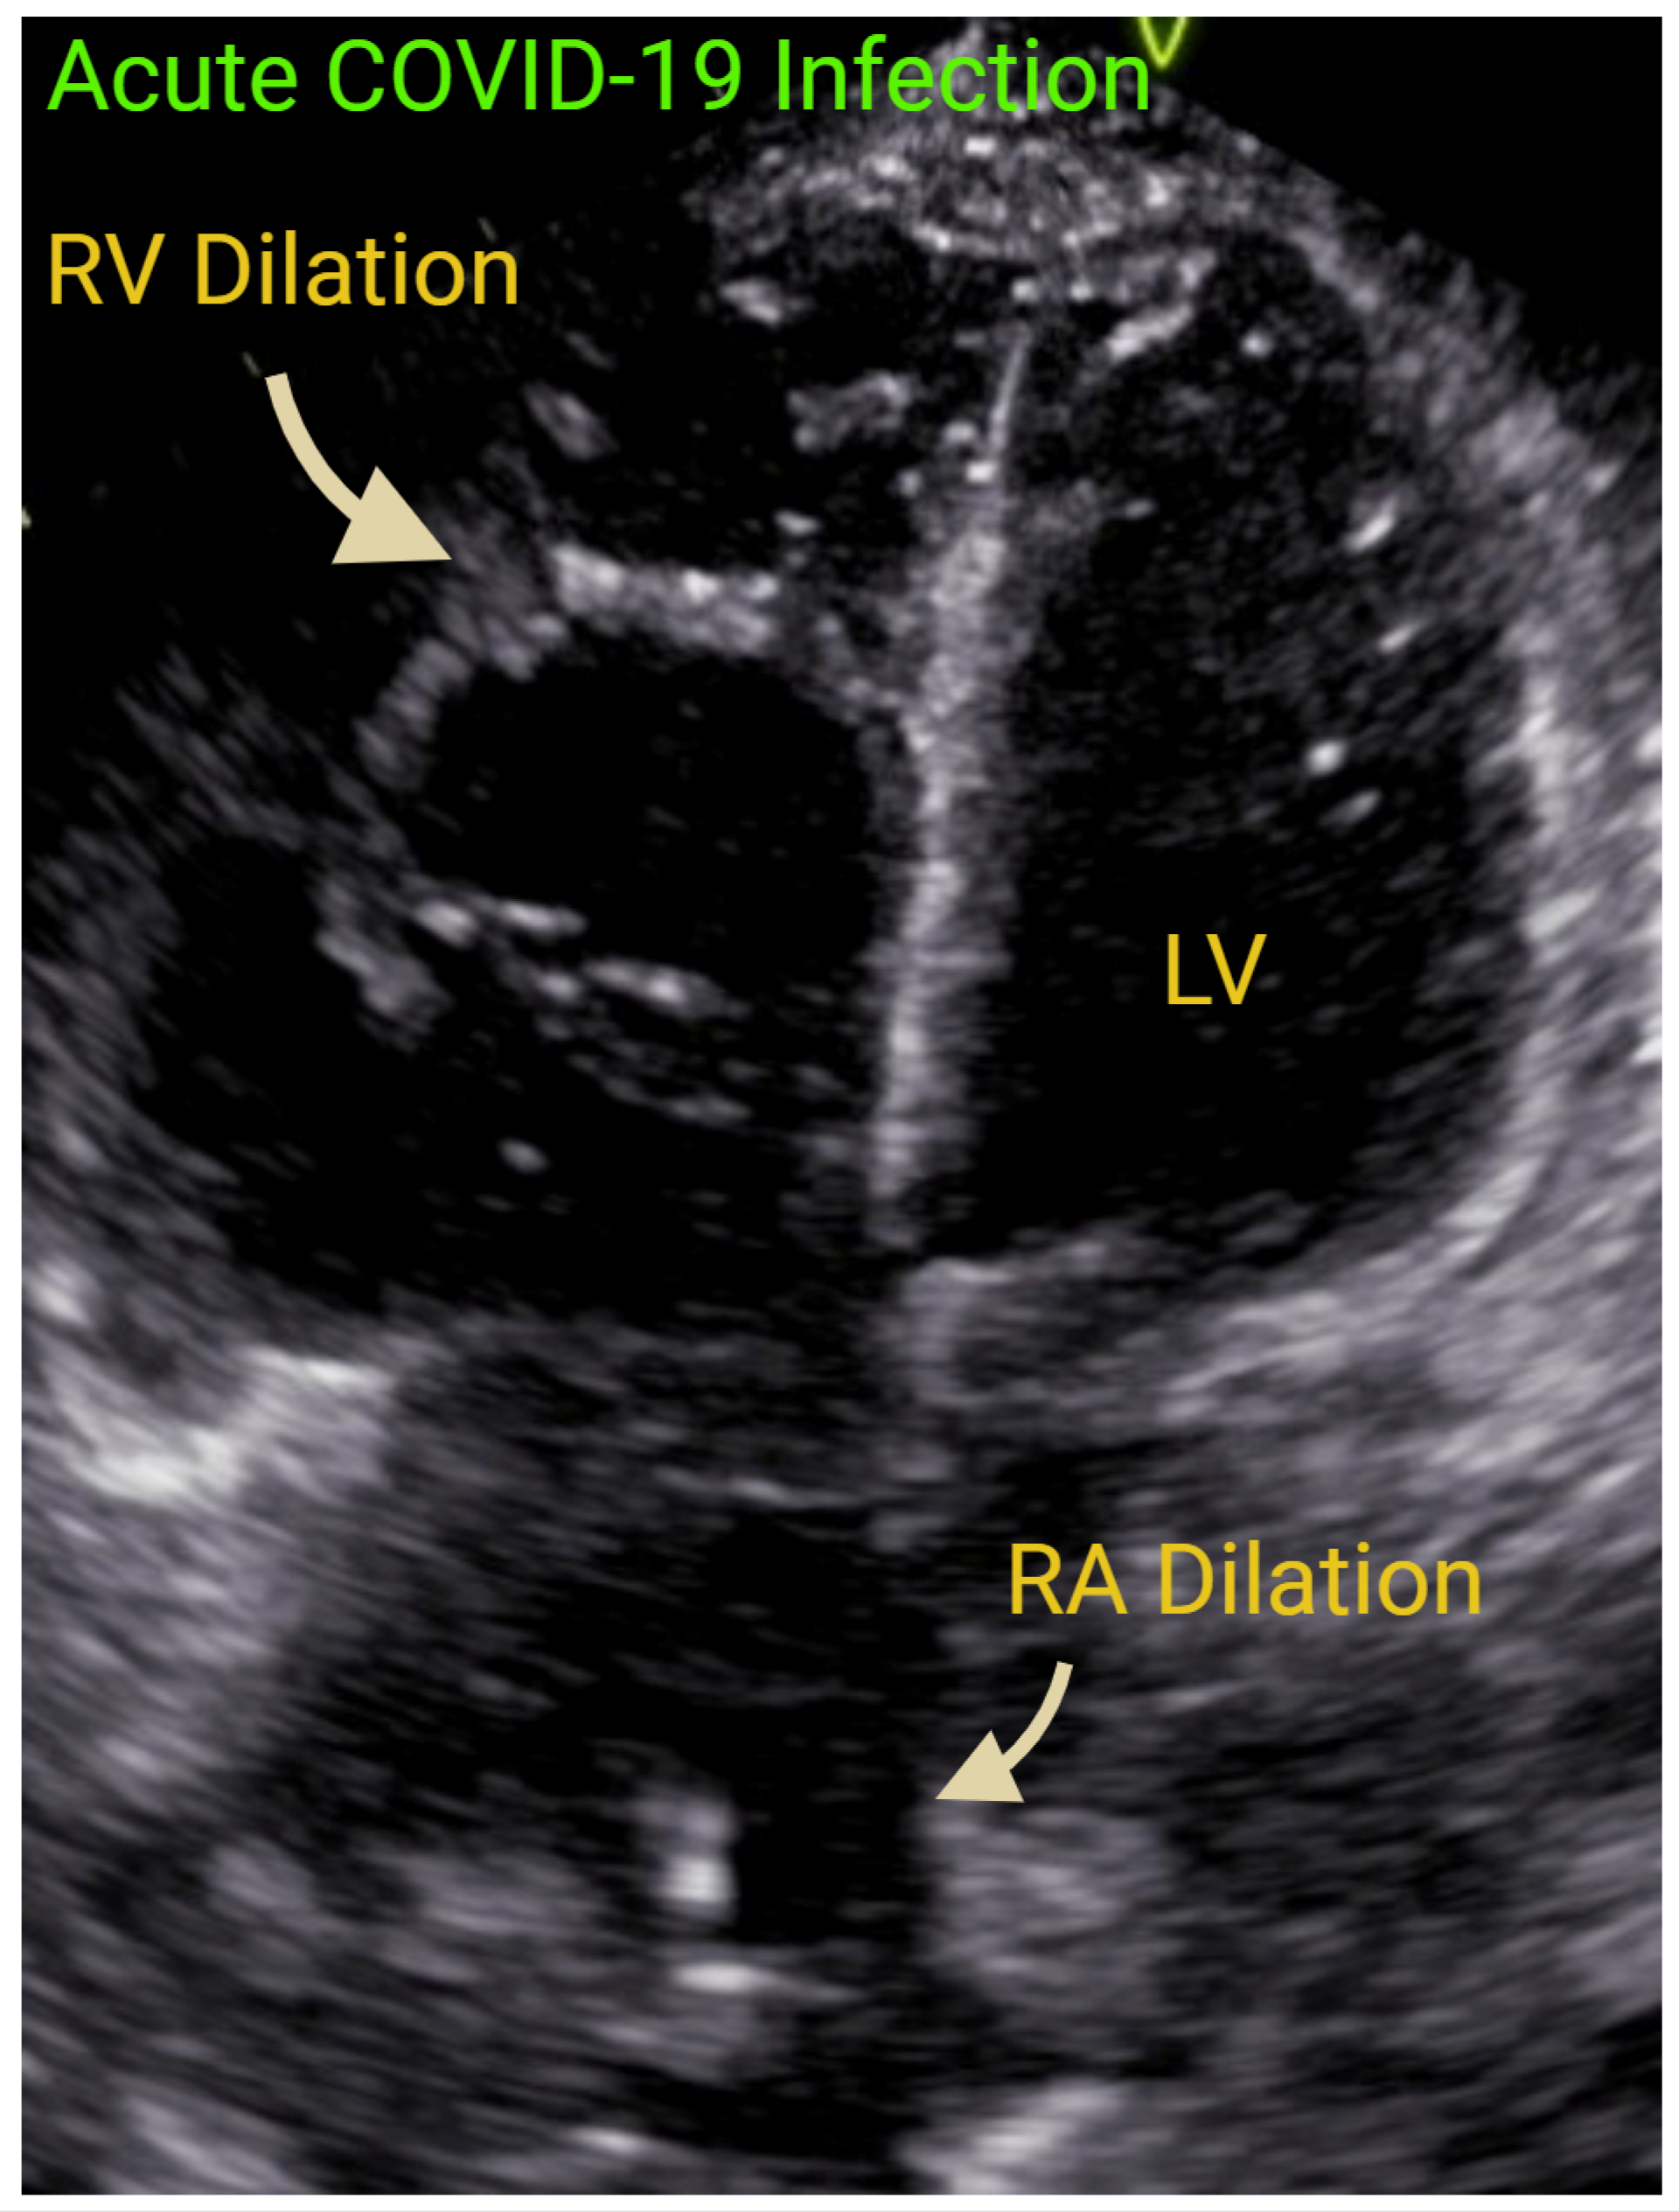

- Dandel, M. Heart-lung interactions in COVID-19: Prognostic impact and usefulness of bedside echocardiography for monitoring of the right ventricle involvement. Heart Fail. Rev. 2022, 27, 1325–1339. [Google Scholar] [CrossRef] [PubMed] [PubMed Central]

- Bleakley, C.; Singh, S.; Garfield, B.; Morosin, M.; Surkova, E.; Mandalia, M.S.; Dias, B.; Androulakis, E.; Price, L.C.; McCabe, C.; et al. Right ventricular dysfunction in critically ill COVID-19 ARDS. Int. J. Cardiol. 2021, 327, 251–258. [Google Scholar] [CrossRef] [PubMed] [PubMed Central]

- Shafiabadi Hassani, N.; Shojaee, A.; Khodaprast, Z.; Sepahvandi, R.; Shahrestanaki, E.; Rastad, H. Echocardiographic Features of Cardiac Injury Related to COVID-19 and Their Prognostic Value: A Systematic Review. J. Intensive Care Med. 2021, 36, 500–508. [Google Scholar] [CrossRef] [PubMed]